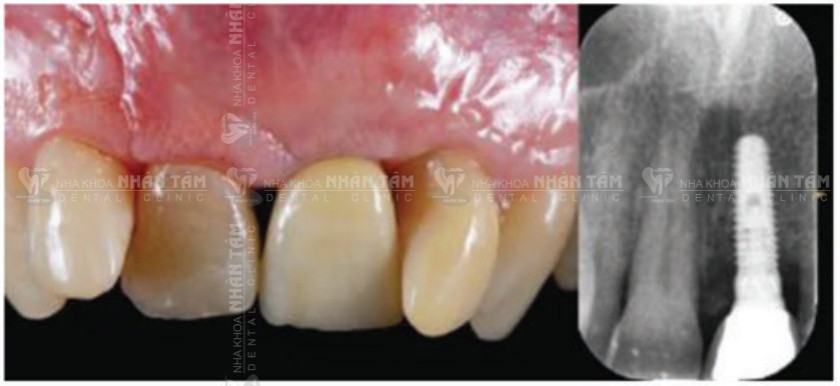

Kết quả: Sau 1 năm theo dõi, tình trạng viêm đã khỏi hoàn toàn, mô nướu khỏe mạnh. Hình chụp X-quang cho thấy tăng mức xương đáng kể và ổn định.

Theo dõi sau 1 năm